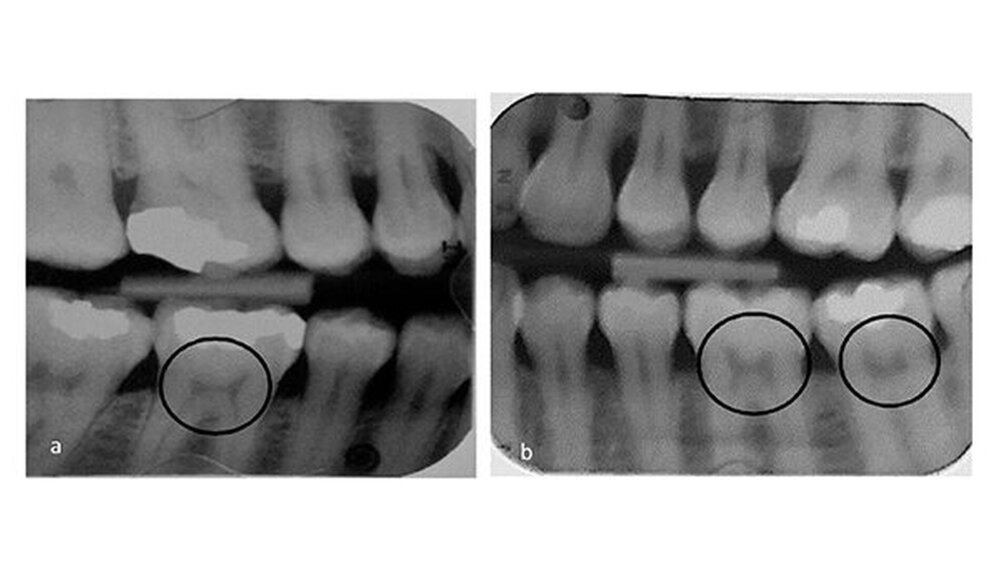

Die Form der Pulpa im gesunden Zahn ähnelt bekanntlich einem Bogen, der von zwei Katzenohren gekrönt wird, während sie bei Personen mit schwerem Vitamin D-Mangel asymmetrisch und verengt ist und typischerweise wie ein Stuhl mit harter Lehne aussieht.

Den Autoren zufolge gehen Vitamin-D-, Calcium- oder Phosphat-Mängel mit Veränderungen der Pulpenkammern aufgrund der abnormalen Mineralisierungen einher. Zellstoffanomalien könnten daher die erste Evidenzstufe für einen zuvor nicht diagnostizierten Vitamin D-Mangel sein.